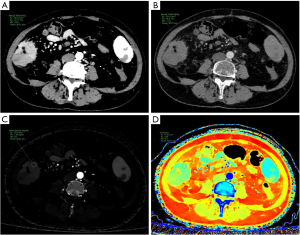

Table 3 and Figure 2 show the results of the SDCT quantitative parameter analysis for the two groups. CT40keV [175.14 (152.90, 194.94) vs. 152.65 (119.29, 176.93) HU, P=0.02], CT120keV (49.19±6.14 vs. 44.19±7.36 HU, P=0.007), IC [1.68 (1.35, 1.84) vs. 1.36 (1.00, 1.64) mg/mL, P=0.02], NIC [0.15 (0.12, 0.18) vs. 0.11 (0.09, 0.14), P=0.002], Zeff [8.23 (8.08, 8.31) vs. 8.09 (7.90, 8.24), P=0.048], NZeff [0.73 (0.71, 0.75) vs. 0.70 (0.68, 0.74), P=0.008], λHU [1.64 (1.32, 1.76) vs. 1.32 (0.98, 1.60), P=0.03] in the arterial phase and AEF [0.74 (0.63, 0.85) vs. 0.60 (0.49, 0.76), P=0.01] were higher in the low-grade TB group than in the high-grade TB group. No significant difference was observed in the spectral characteristics of the venous phase between the two groups (P>0.05). Figures 3,4 show spectral CT multiparametric images of high-grade and low-grade TB in CRC, respectively.

Elevated spectral CT parameters often signify an enhanced vascularization in tumors, correlating with accelerated tumor proliferation and increased malignancy (20). Theoretically, spectral characteristics for high-grade TB colorectal tumors should exceed those of low-grade TB, attributable to the elevated tumor grade, enhanced invasiveness, and augmented blood supply in the high-grade group. Our study indicated that spectral parameters during the arterial phase and AEF for the high-grade TB group were inferior to those of the low-grade TB group. We propose that this gap may be ascribed to many factors: TB is associated with more aggressive characteristics in CRC, including poor differentiation, vascular invasion, and elevated TNM stage, which are more common in the high-grade TB group (33). In addition, inadequate differentiation in high-grade TB CRC results in less functional vascularization and a decreased blood supply relative to well-differentiated tumors. Vascular invasion and microthrombosis, often seen in high-grade TB tumors, may further diminish arterial blood flow and venous return. Moreover, the elevated Ki-67 expression seen in high-grade TB tumors facilitates accelerated tumor growth and proliferation, resulting in inadequate blood supply, cystic degeneration, and necrosis. These characteristics may hinder the definition of ROI (36), and lead to diminished spectral parameters in the high-grade TB group.